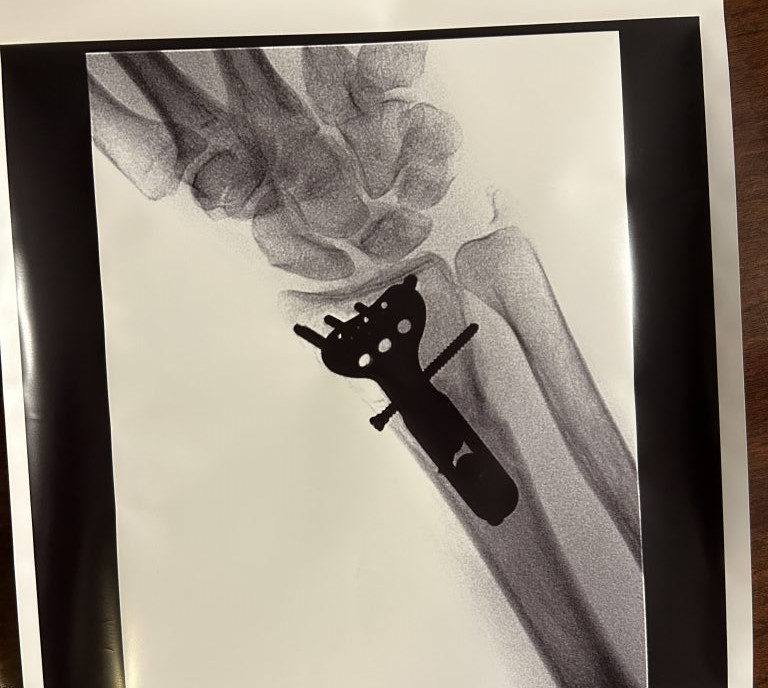

I was in good hands - literally. Dr. Wolfe has so many impressive credentials; I knew that this was the best doctor I could see for my wrist fracture. The surgery happened a few days later, and everything went smoothly. I returned for the scheduled follow-ups, and at one point, Dr. Wolfe discussed the option of removing the hardware, to which I happily agreed.

It has been over three months since the hardware was removed (12/19/23), and I am actually doing push-ups (something I never did before the fall). Every day that passes, I thank God that Dr. Wolfe was my surgeon. If you have any type of wrist issue - stop your search. You won't find a better doctor than Dr. Wolfe and the crew at HSS. They are all really and truly wonderful!